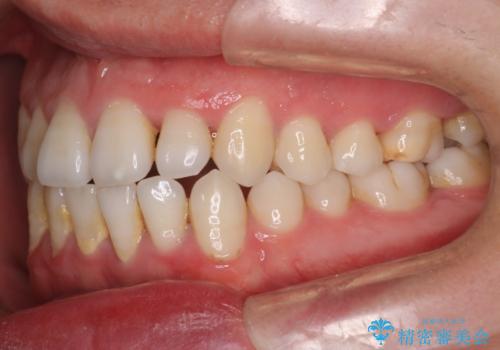

- 前歯のすきっ歯が気になると来院された患者様です。

前歯の隙間をマウスピース矯正(インビザライン)を使用して、閉じていきました。